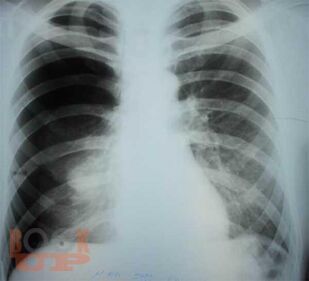

Спонтанный пневмоторакс

Ханнанов Н. И. Спонтанный пневмоторакс : учебное пособие для врачей / Н. И. Ханнанов, В. В. Фаттахов, М. Н. Насруллаев. - Казань : КГМА, 2020. - 40 c. - Текст : электронный // ЭБС "Букап" : [сайт]. - URL : https://www.books-up.ru/en/book/spontannyj-pnevmotoraks-16035604/ (дата обращения: 01.05.2026). - Режим доступа : по подписке.